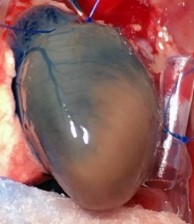

Chronic Ischemia (MI)

4-7 Days Post MI Average 30% Infarct Area. Model Developing Athero